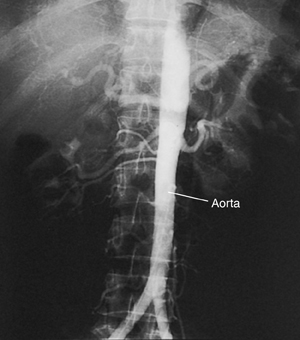

Aortic Angiogram

An aortic angiogram is a test that takes pictures of the aorta. This is the main blood vessel that carries blood from your heart to the rest of your body. The test can show problems with your aorta. These include a blockage or an aneurysm (a balloon-like bulge in the wall of the aorta).

Once the catheter is in the right place, contrast fluid (dye) is sent through the catheter. X-ray pictures are then taken of the aorta. The contrast fluid (dye) makes the aorta easier to see on the pictures.